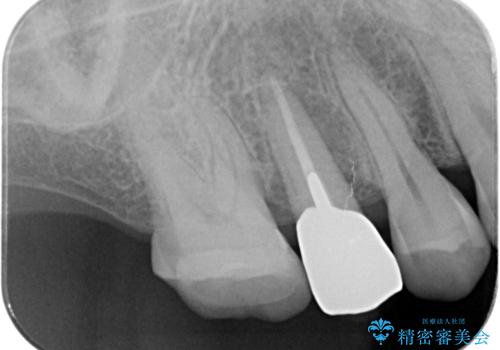

かぶせ(以下クラウン)を外してみたところ、神経のない支台となる歯が折れてしまい抜歯を余儀なくされる状況でした。

抜去後の機能回復方法としてインプラント、入れ歯以外の方法を希望されたためブリッジでの咬合機能回復を行っていくこととなりました。